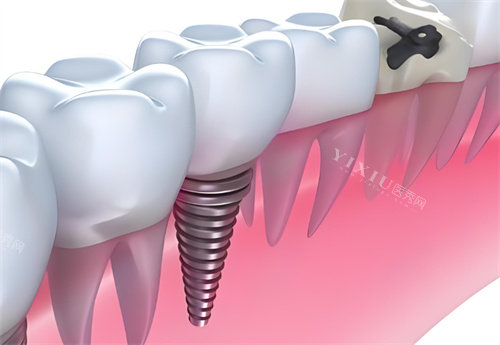

种植修复类

韩国进口种植体:4980元/颗起

瑞士ITI种植系统:12800元/颗起

全口半固定种植修复:68000元起

即刻负重种植术:15800元/颗起

骨增量手术(上颌窦提升):4500元起